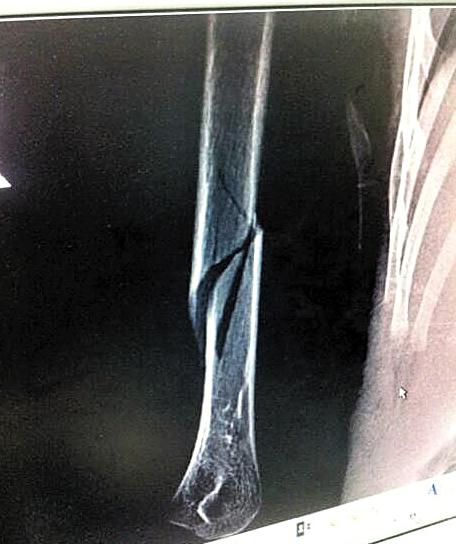

男童骨折照片

4岁的小劲右手打着石膏和夹板,他是位于广州市萝岗区的南方中英文学校?。?)班的学生,但已经一个月没有上幼儿园了。原因是7月14日,他的右手上臂被老师弄伤,导致骨折。在广州市正骨医院提供的放射检查报告单上,可以看见小劲右手上臂骨头中间有一处明显断裂。